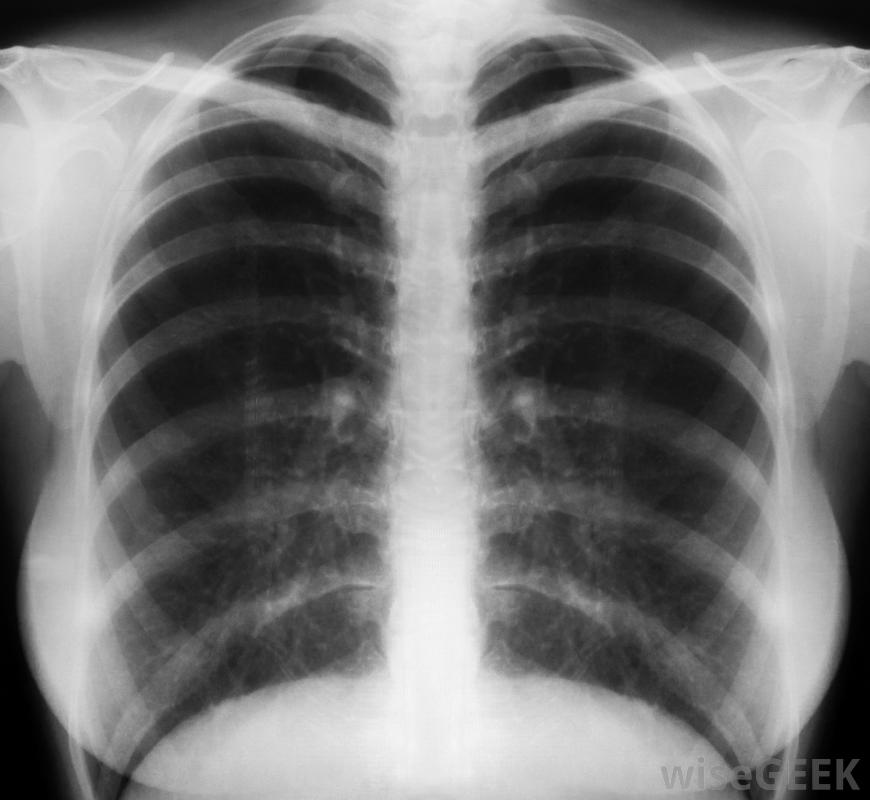

胸部x光片可以帮助确定上腔静脉综合征的严重程度。肺部、胸部的恶性肿瘤,胸部的甲状腺和淋巴结是上腔静脉综合征的主要原因。静脉没有得到很好的保护,很容易被不断增长的肿瘤压迫。血凝块、甲状腺肿和心脏动脉瘤也会限制正常的血液流入心脏。此外,未经治疗的细菌和病毒感染,如肺结核梅毒有时会导致上腔静脉炎症和阻塞。

上腔静脉将上半身的血液输送回心脏,随着肿瘤或其他疾病的发展,疾病会逐渐发展,虽然急性上腔静脉综合征的病例可能是由血液凝固引起的。在疾病的早期,病人可能会出现头晕、头晕、经常头痛和轻微的视力问题。随着血液流动进一步受限,面颊、鼻子、手和手臂会出现红肿。最终,颈部和面部肿胀并开始变蓝喉咙肿胀会导致严重的呼吸问题,如果不立即缓解,可能导致昏迷和脑损伤。怀疑进行性上腔静脉综合征的医生可以对患者的喉咙和面部进行体检,并检查是否有血压异常的迹象。胸部x光片和计算机轴位断层扫描(CAT)可以显示梗阻的原因和严重程度。医生通常会给病人服用类固醇或利尿剂来缓解立即出现的肿胀症状,然后确定治疗的最佳方案。化疗或放疗通常用于消除胸部或肺部的癌性肿瘤。抗凝药物可以缓解血栓,细菌感染可通过口服或静脉注射抗生素来治疗。由于心脏和周围结构的脆弱性,很少进行手术。非癌症患者的预后非常好,大多数人在不到一个月的时间内就可以从症状中恢复过来。癌症患者可能需要接受持续的治疗和监测以确保癌症不会扩散到身体的其他部位。